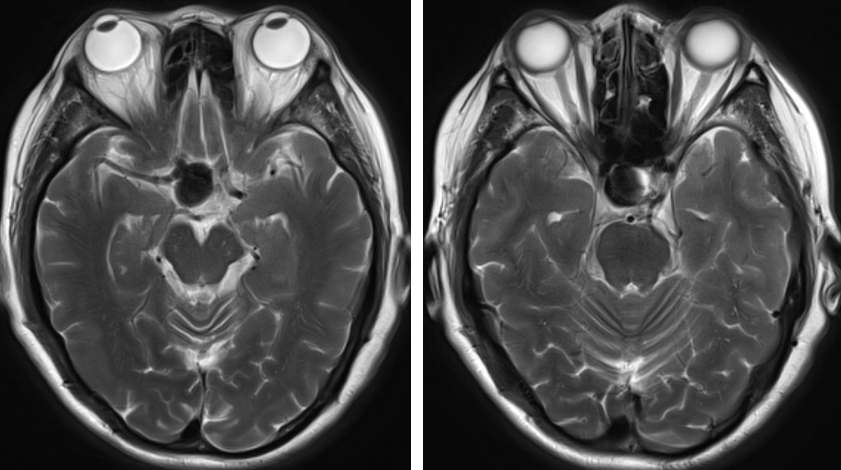

对于有2次以上头部外伤病史导致慢性硬膜下血肿形成者, 或血肿范围较广者, 即使颅脑CT 已经明确诊断, 术前仍有必要再行颅脑MRI检查。

增强MRI扫描对发现高龄脑萎缩、血肿分隔多房、包膜形成、血肿机化等有重要作用。

头颅MRI